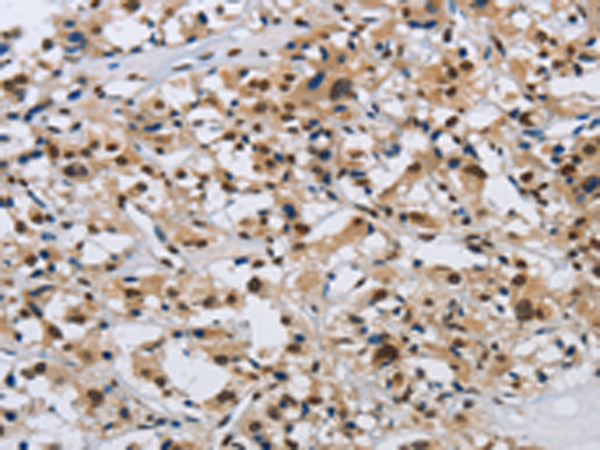

分类: 科研抗体货号: P04967别名: GPAPP; IMP 3; IMP-3; IMPA3应用: IHC反应种属: Human, Mouse, Rat